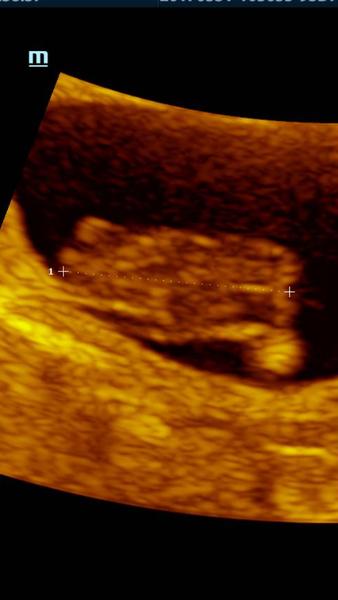

baby tak nasa mala rybka (na fotke zo sona tak vyzera :D ) ma uz 2,06cm srdiecko bije o stosest, termin sa posunul o dva dni neskor podla velkosti a tym padom presne viem kedy sme si zamiesili :D 13.2. o pol5 rano ked sa mi nedalo spat a zobudila som si chlapa, ze mam chut :D riadna nahoda, ze? 🙂